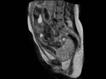

A berlini Charité orvosai olyan felvételt hoztak nyilvánosságra, amely egy szülés végső fázisát még sosem látott módon- nyitott MRI készülék segítségével - szemlélteti valós időben.

A kis Duncan születését ugyan már 2010 novemberében megörökítették, de a felvételeket csak pár napja láthatjuk a világhálón. A 24 éves anya egy speciális nyitott MRI készülékben feküdt a szüléskor, amelyben némileg mozogni is tudott, és az orvosok is könnyen el tudták látni.

Szülésről készítettek már korábban is röntgensugarakkal, illetve ultrahanggal felvételeket, azonban ez a mostani képfelvétel annyiban újdonság, hogy az igazi valóságot, valós időben mindenféle egészségkárosító hatás nélkül képes bemutatni.